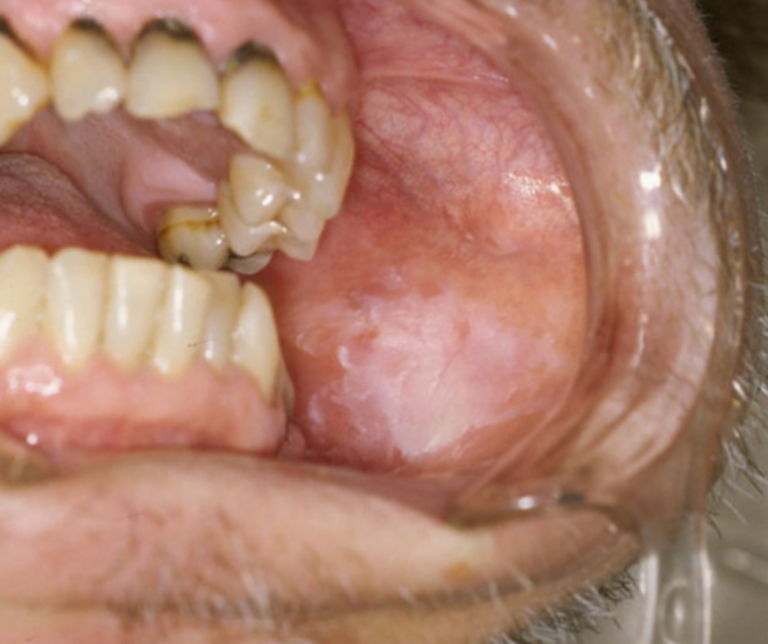

治らない口内炎・色の変化(口腔粘膜疾患)

もっとも注意深く拝見するのが、単なる口内炎と見分けがつきにくい異変です。

白板症(はくばんしょう)や紅板症といった「がん化する可能性のある状態(前がん病変)」や、初期の口腔がんの可能性があります。

痛みがないことも多く、特に「2週間以上、形や色が変わらずに残っている」場合は要注意です。

白斑(はくはん)

歯茎や頬の裏に、こすっても取れない「白い板」のような模様がある。

表面の状態、境界線を詳細に観察します。

少しでも疑わしい場合は、即座に専門病院での組織検査を手配します。